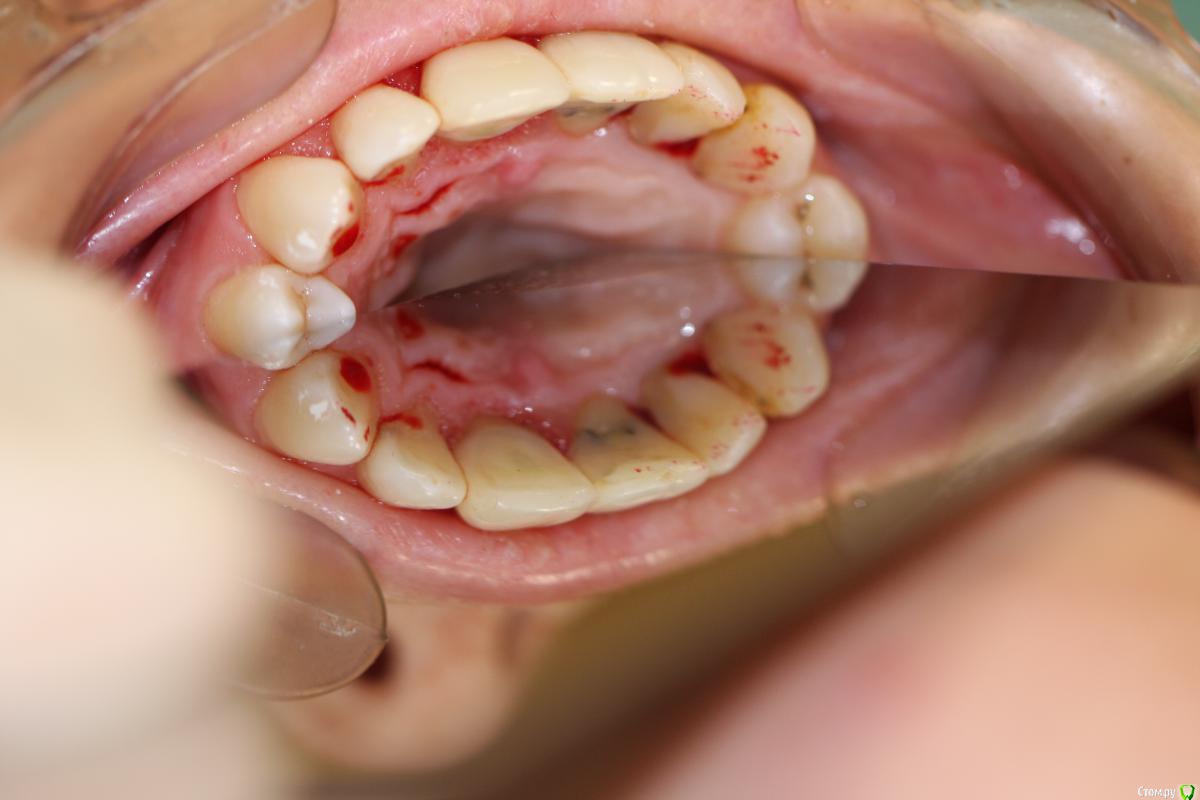

skeettrap Опубликовано 19 марта, 2016 Поделиться Опубликовано 19 марта, 2016 Работа из категории - для души. Попутно сделан кариес у 12 с медиальной стенки , 21 - только подполирована медиальная стенка. 3 Ссылка на комментарий

krokomot Опубликовано 19 марта, 2016 Поделиться Опубликовано 19 марта, 2016 Для бюджета, очень даже не плохо, учитывая общую ситуацию во рту. В посте не хватает кадрирования фотографий ( выровнять, обрезать), ну конечно рентгеновского снимка. Ссылка на комментарий

skeettrap Опубликовано 20 марта, 2016 Автор Поделиться Опубликовано 20 марта, 2016 Для бюджета, очень даже не плохо, учитывая общую ситуацию во рту. В посте не хватает кадрирования фотографий ( выровнять, обрезать), ну конечно рентгеновского снимка.Спасибо за отзыв. Фотограф я начинающий. Буду стараться.По поводу сломаться - скорее сломает 21,22 (мертвые), если не появится больше. Этот остался в яблоке.Про эстетику: 21,22 с серым оттенком, 12 - А2 .МК будет выделяться. Емах понятно лучше на 11,21,22 с соответствующей подготовкой,но ей это не потянуть.А так , по-моему, хорошее решение с возможностью улучшения в любой момент. Ссылка на комментарий

Доктор Дмитрий Опубликовано 20 марта, 2016 Поделиться Опубликовано 20 марта, 2016 Сомнительная работа с точки зрения функции, зубы разные по форме и по цвету немного тоже. Ссылка на комментарий